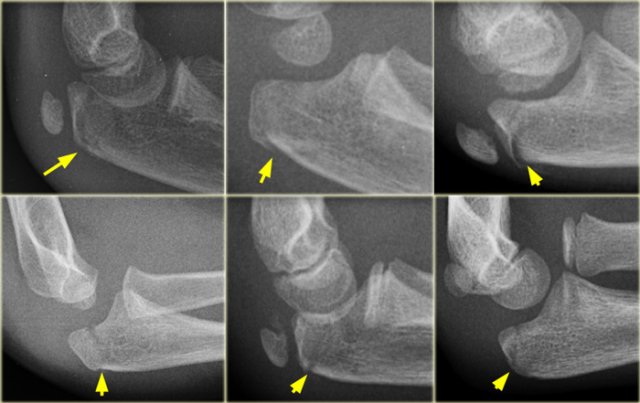

Olecranon fractures

Olecranon fractures in children are less common than in adults. As discussed above they are associated with radial neck fractures and radial dislocations.

Olecranon fractures (2)

Do not mistake the apophysis or its separate ossification centres for a fracture.

The apophysis has undulating faintly sclerotic margins.

The growth plate usually has a different oblique course compared to a fracture-line.

Olecranon fractures (3)

On the left some examples of fractures of the olecranon.

Notice how subtle some of these fractures are.